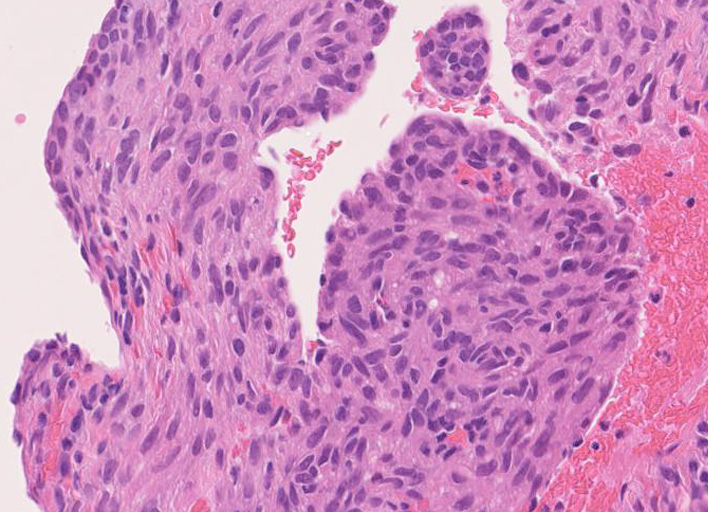

LAMの肺病変

嚢胞周囲または肺血管, リンパ管, 細気管支にそうLAM cellの浸潤, 集簇を特徴とする。LAM cellには2種類が認められ, 小型紡錘形細胞と細胞質の豊富な類上皮様細胞があり, 紡錘型は主に集簇巣の中心に存在し増殖能が高い。 類上皮様LAM cellは辺縁部に多く, 増殖能は低いがHMB45を強く発現している。

LAM cellの免疫染色--SMA, desmin, vimentin(vimentinはいつも陽性とはならない)が陽性となりmuscle lineageであるが典型的な筋細胞と異なり,

嚢胞形成はLAM cellの増殖と関連しており, 細胞が産生するmatrix metalloproteinases(MMPs)による組織破壊によるらしい。